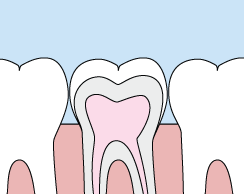

Crowns

Crowns are a restorative procedure used to improve your tooth’s shape or to strengthen a tooth. Crowns are most often used for teeth that are broken, worn, or have portions destroyed by tooth decay.

A crown is a "cap" cemented onto an existing tooth that usually covers the portion of your tooth above the gum line. In effect, the crown becomes your tooth’s new outer surface. Crowns can be made of porcelain, metal, or both. Porcelain crowns are most often preferred because they mimic the translucency of natural teeth and are very strong.

Crowns or onlays (partial crowns) are needed when there is insufficient tooth strength remaining to hold a filling. Unlike fillings, which apply the restorative material directly into your mouth, a crown is fabricated away from your mouth. Your crown is created in a lab from your unique tooth impression, which allows a dental laboratory technician to examine all aspects of your bite and jaw movements. Your crown is then sculpted just for you so that your bite and jaw movements function normally once the crown is placed.